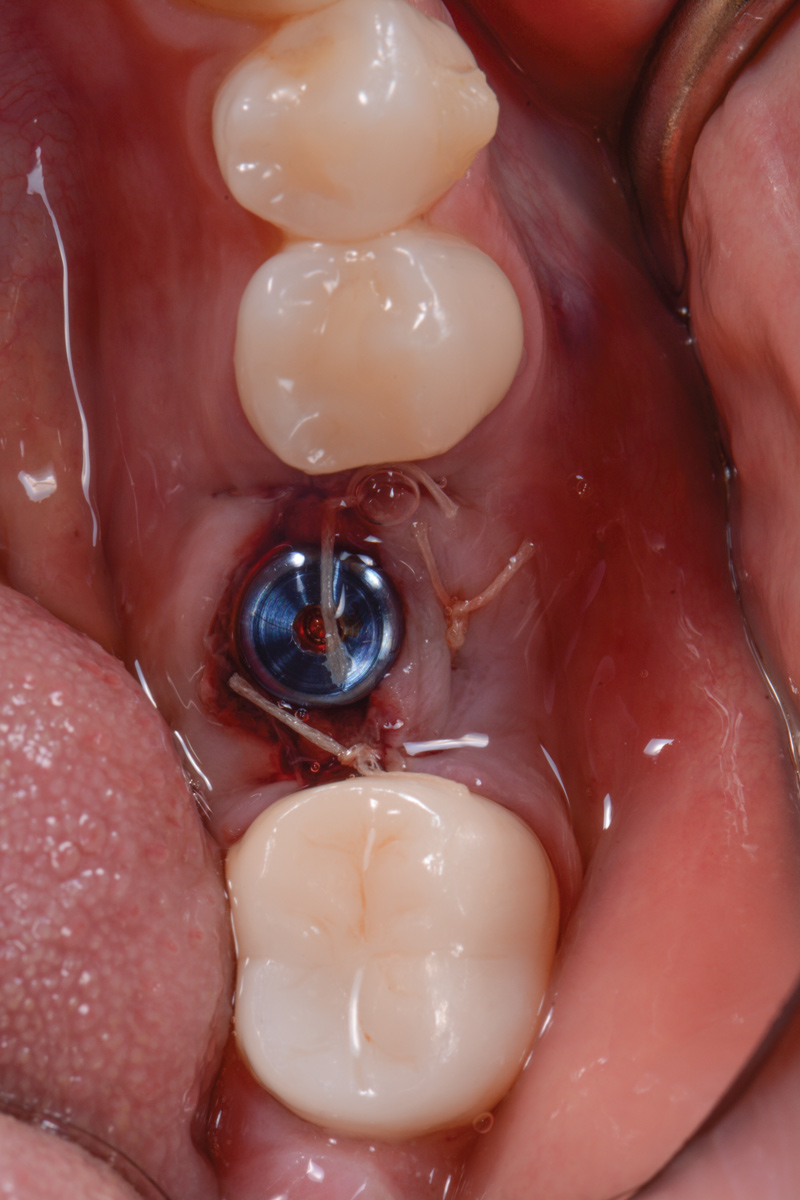

The following day, the patient presented for an emergency, reporting she began to bleed after she left the office and had continuous bleeding that day and night. Vital signs were normal (blood pressure was 115/65 mmHg, and pulse was 53 beats per minute). The first attempt to control the bleeding included having the patient bite on wet collagen wound dressing and alternate using wet- and dry-gauze compression for 30 minutes. After the removal of the collagen wound dressings, the bleeding restarted spontaneously. The sutures were then removed, and a collagen wound dressing was placed under the flap. Two single interrupted sutures were used, and a third suspended suture was placed around the healing abutment to obtain compression in the area. The patient was observed for 1 hour. During this time, wet-gauze compression was used on the area until the bleeding stopped. The patient was then dismissed and told to reapply gauze with pressure if bleeding recurred (Figure 1 through Figure 5).

Fig 4. Wound dressing secured with two single interrupted sutures and one suspended resorbable suture.

Figure 4